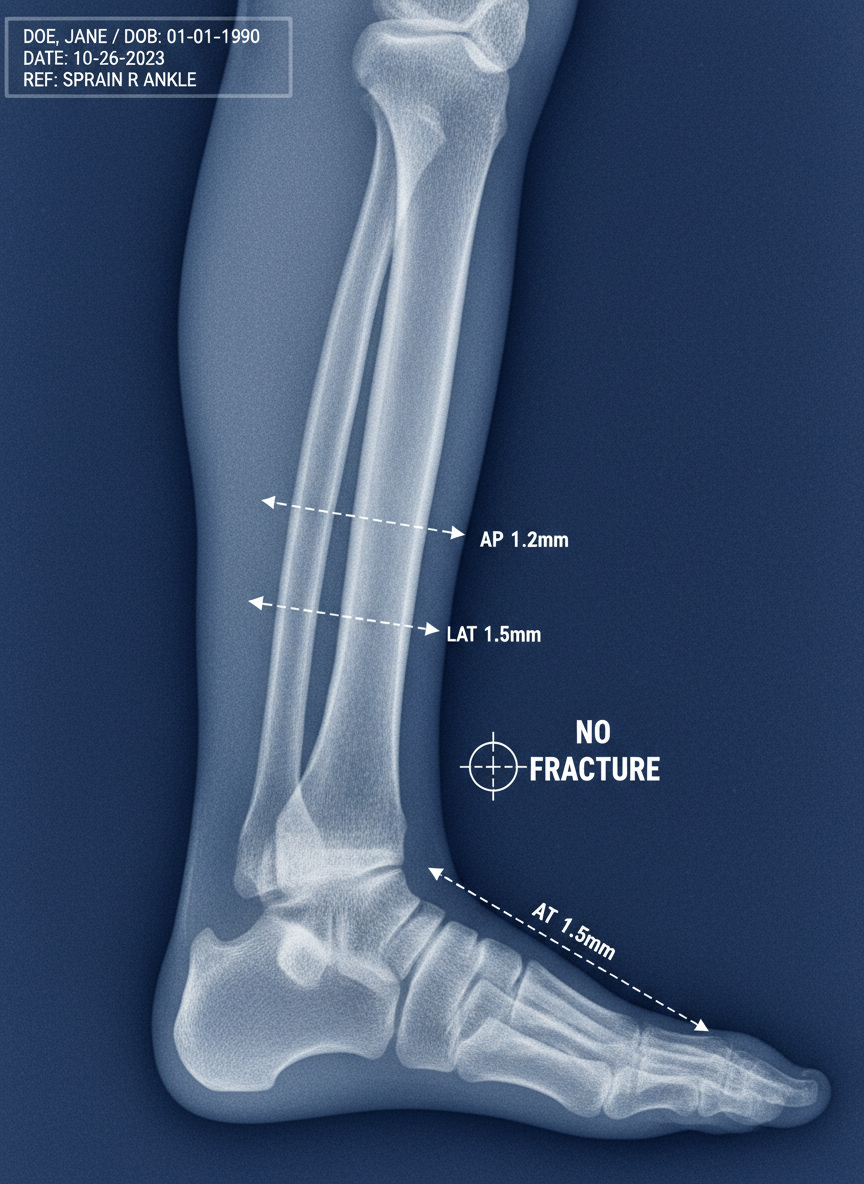

⚠️ 주의! 섣부른 판단은 금물! RICE 요법은 응급처치일 뿐이에요. 통증이 심하거나 멍이 크고, 체중 싣기 어렵다면 반드시 병원에 방문하여 진단과 치료를 받아야 합니다.

Q1: 발목을 접질렸는데 병원에 꼭 가야 할까요?

A1: 통증이 심하거나 부기가 가라앉지 않고, 체중을 싣기 어렵다면 반드시 병원에 방문해야 합니다. 골절이나 인대 파열일 수도 있어요. 전문가의 진단이 중요합니다.